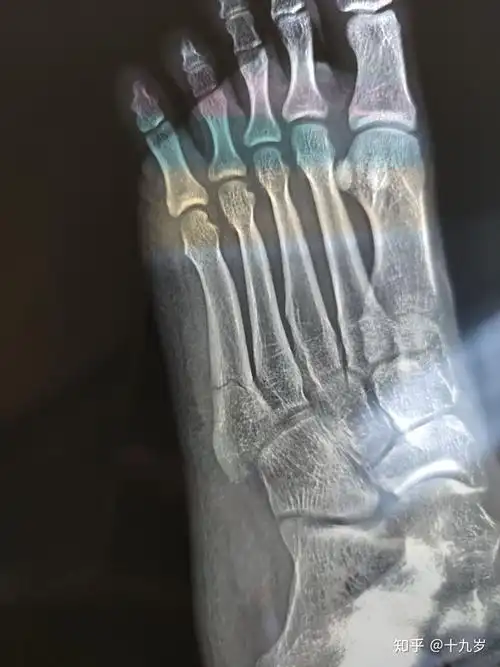

第五跖骨骨折快两个月了都没好